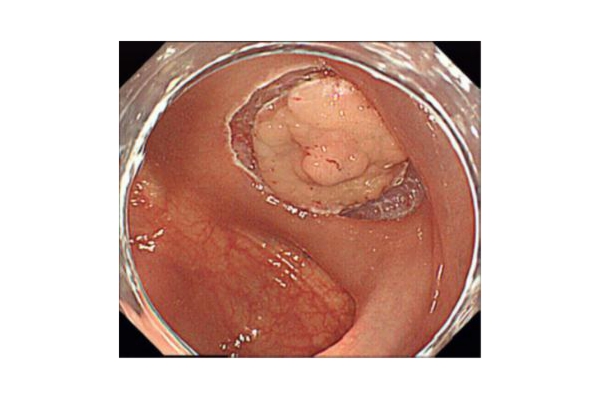

《胃ESDの実際》

食道表在癌、早期胃癌の治療法として当科では積極的にESDを行っています。ESDとは内視鏡的に使用可能な高周波メスを使って、粘膜下層のレベルで病変を剥がし取る手技です。早期の小さな癌に対しては今までも内視鏡治療が行われてきましたが、ESDにより従来の内視鏡治療法(EMR)では切除困難であった大きな病変や、瘢痕を認める病変を一括切除できるようになりました。体を切開することなく組織も温存できるため、患者の身体的負担が少ない低侵襲医療のひとつです。

食道ESDは年間約15例、胃ESDは年間約40例ほど行っております。